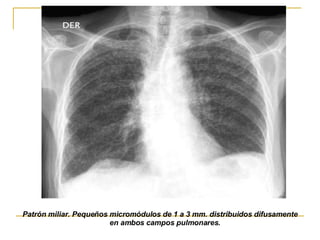

TUBERCULOSIS MILIAR resultado de la diseminación hematógena fases iniciales, normal. una semana después ,presencia de un halo difuso, mal definido en ambos pulmones y posteriormente la imagen típica de nódulos pulmonares miliares bien definidos. Afectación es de todos los campos pulmonares, existen adenopatías hiliares

Patrón miliar. Pequeños micromódulos de 1 a 3 mm. distribuidos difusamente en ambos campos pulmonares.